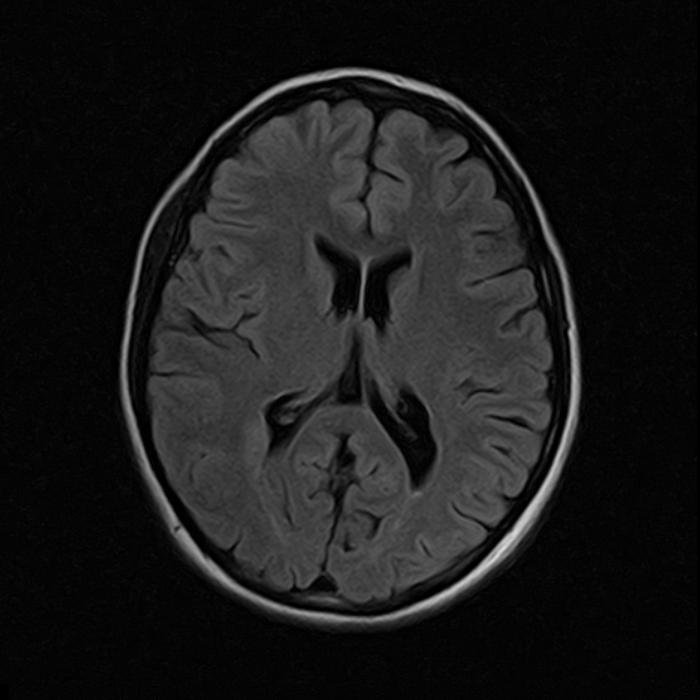

По итогам исследования, на снимках суб- и супратенториальных областей мозга выявлены единичные (в количестве трех) перивентрикулярные очаги: справа на уровне задних рогов боковых желудочков размером до 6х3 мм, слева до 5х3 мм и сверху правого бокового желудочка до 5 мм, без следов перифокального отека (они слабо гиперинтенсивные на Т2 FLAIR и Т2 ВИ, изоинтенсивные на Т1 ВИ и DWI). Других очаговых изменений в веществах больших полушарий, ствола, мозолистого тела и мозжечка не обнаружено.

МРТ для диагностики перивентрикулярного лейкоареоза головного мозга